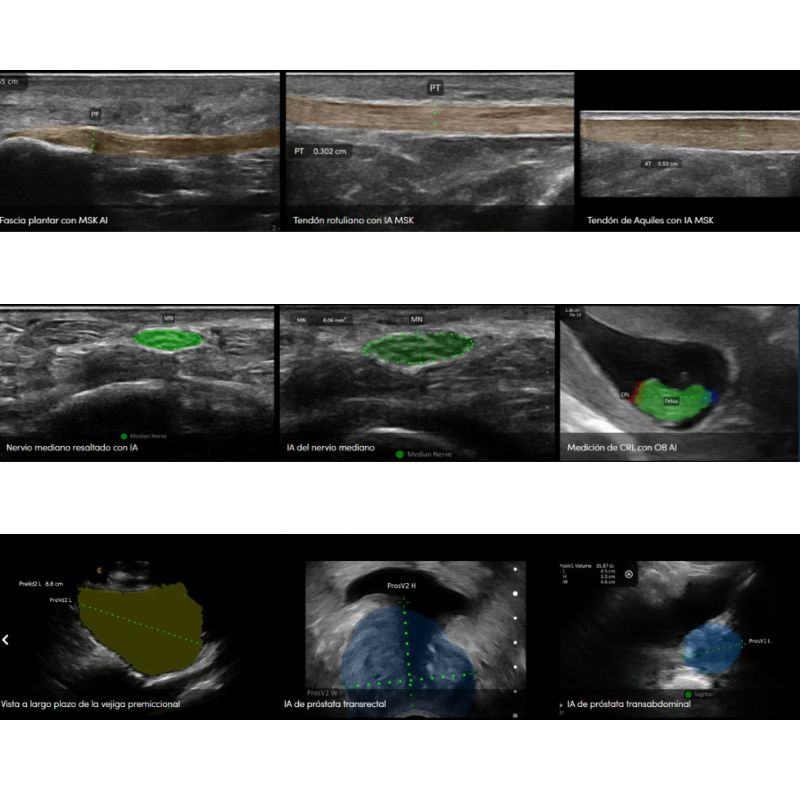

Clarius te permite identificar la anatomía con precisión, diagnosticar patologías con confianza y guiar procedimientos en tiempo real. Impulsado por inteligencia artificial y equipado con 192 elementos piezoeléctricos y ocho formadores de haz, Clarius HD3 ofrece un rendimiento excepcional en un diseño compacto y fácil de usar. Además, con su conexión WIFI directa a dispositivos móviles iOS o Android, olvídate de los cables y las limitaciones.